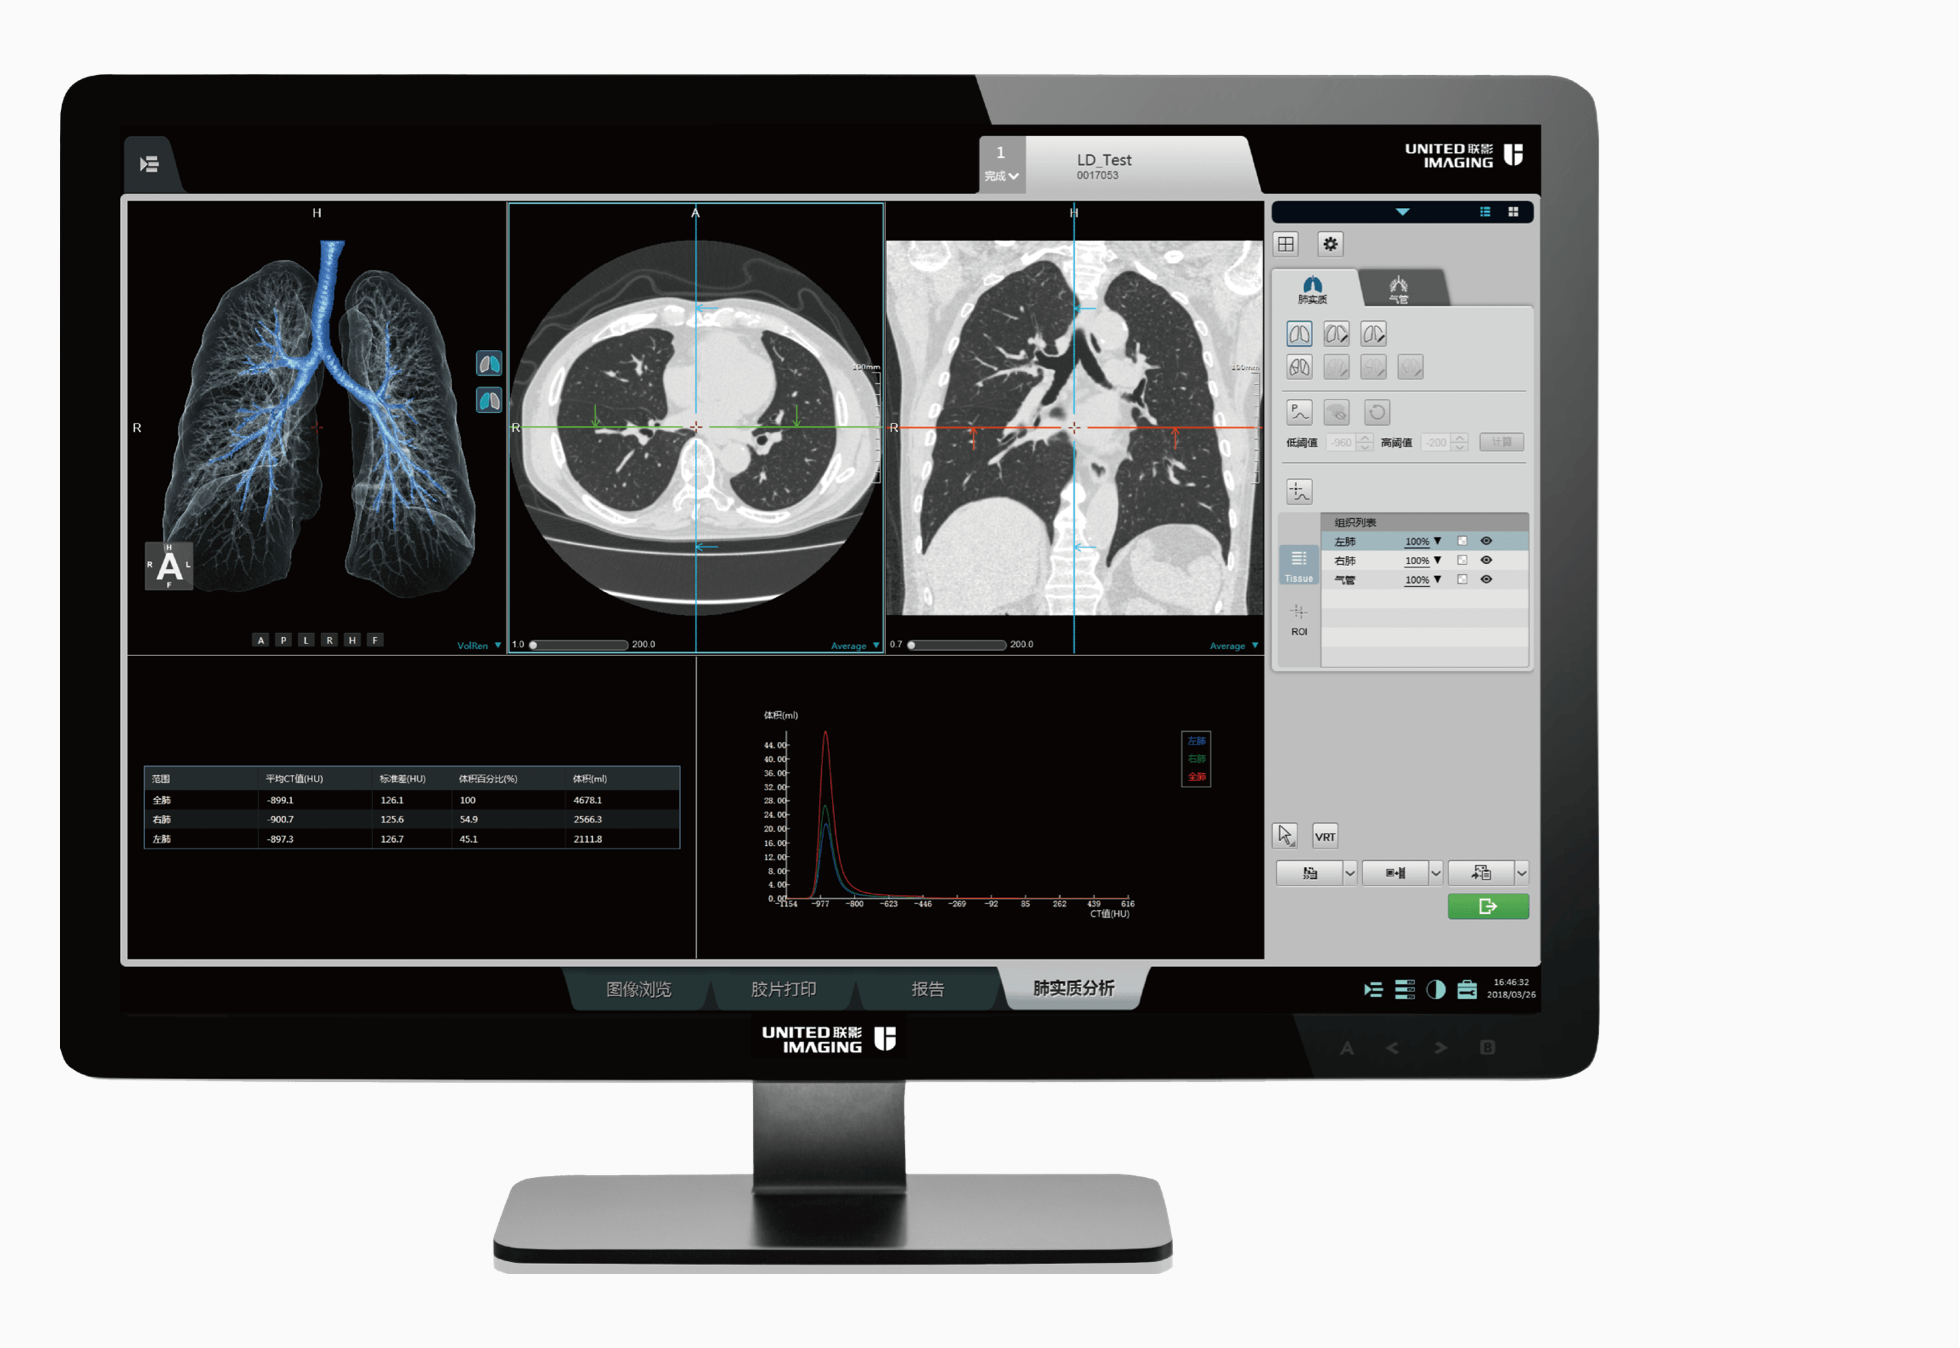

高端硬件

5.3MHU

大热容量球管,轻松应对高通量检查

50kW

大功率高压发生器,带来源源不断的澎湃动力

40排时空探测器

22mm覆盖,0.55mm层厚,卓越空间分辨率与密度分辨率兼而得之

70kV扫描模式

大幅降低辐射剂量,提高造影剂对比度,使微小病变等临床应用难点被突破